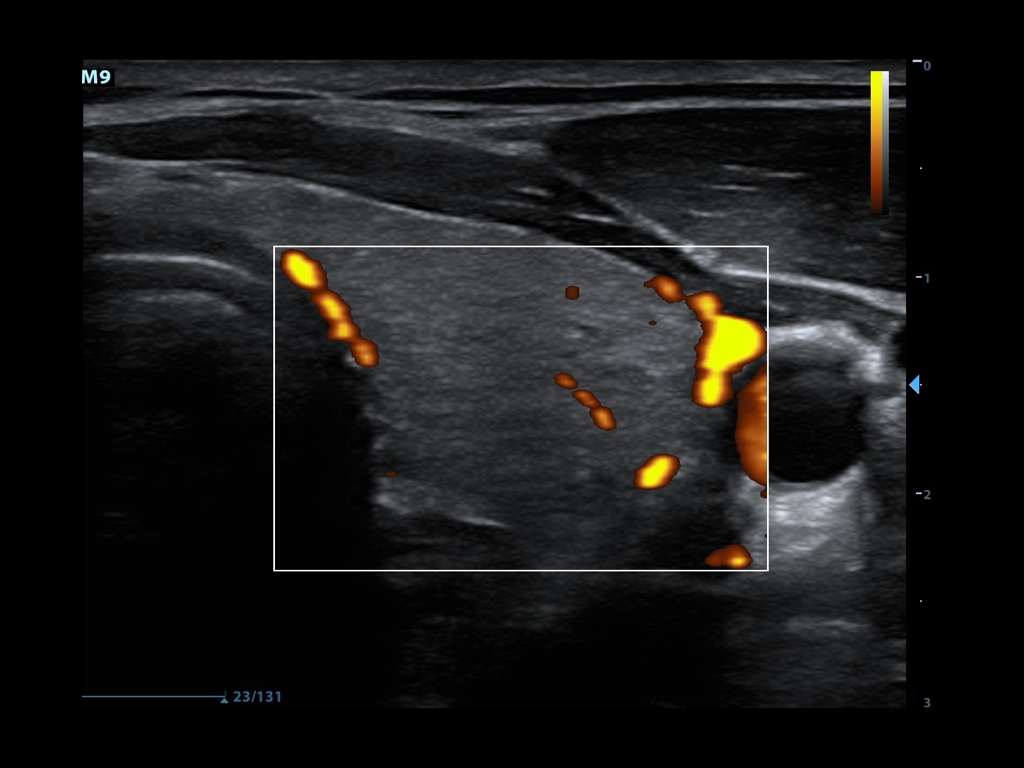

- Power Doppler looks only at the amplitudes of the returning frequency shifts.

- It does not examine flow velocity or the direction of flow

- This allows for detection of movement in very low flow states (Figure 4)

- This is of use when examining vascular emergencies such as testicular or ovarian torsion

- Figure 4. Power doppler showing blood flow in thyroid tissue